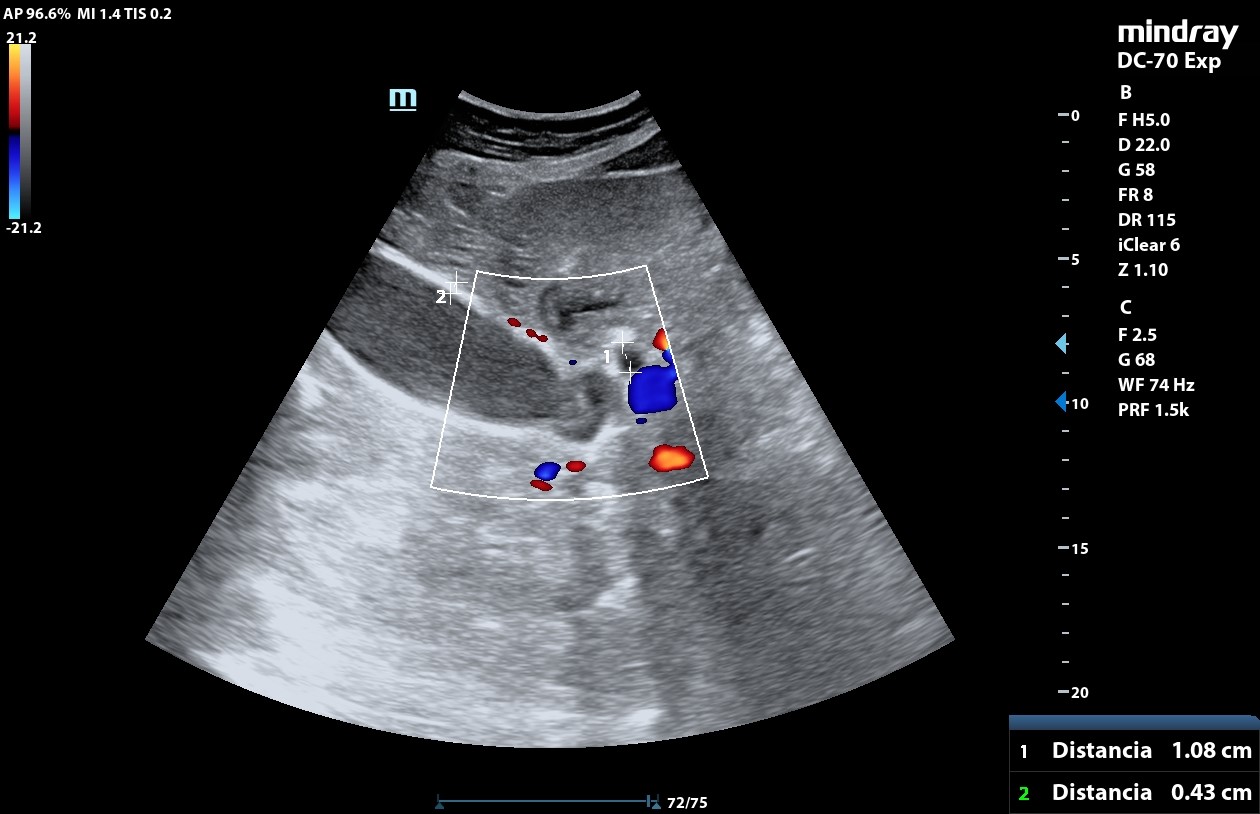

• POCUS: aumento tamaño de la vesícula biliar, eje longitudinal mayor de 11,19 cm, con pared vesicular engrosada de 0,43 cm y dilatación de la vía biliar. En su interior hay material ecogénico que no deja sombra posterior, compatible con barro biliar. No objetivo páncreas por interposición de gas intestinal. No presencia de líquido libre.